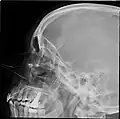

CT scans, radiographs (X-rays) and other illustrations

Paranasal sinuses radiograph (lateral) -